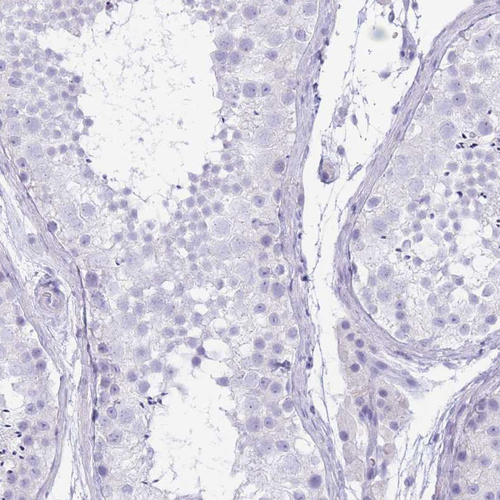

Immunohistochemistry analysis in human adrenal gland and kidney tissues using HPA048979 antibody. Corresponding CYP21A2 RNA-seq data are presented for the same tissues.